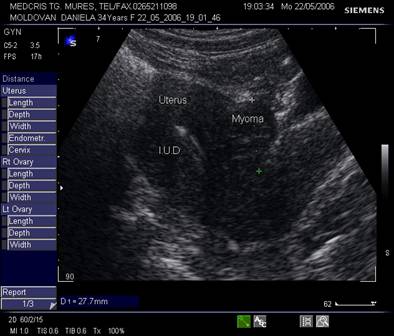

evidentierea dispozitivelor intrauterine

Fig. nr.354. Dispozitiv intrauterin la ecografia abdominala in sectiunea sagitala